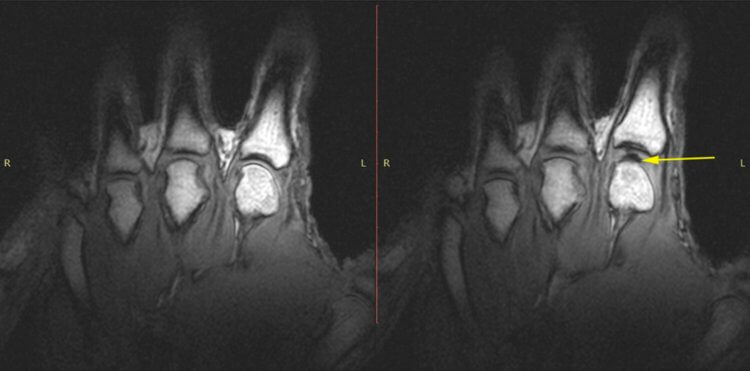

В 2015 году в попытках расставить все «точки над i» Грег Кавчук из Альбертского университета в Канаде и его коллеги использовали МРТ-сканер для записи того, что происходит в пальце добровольца, который часто хрустел костяшками.

МРТ сканирование пальцев добровольца во время «хруста». На изображениях можно увидеть внезапное появление выпуклости в суставе, когда тот «захрустел».